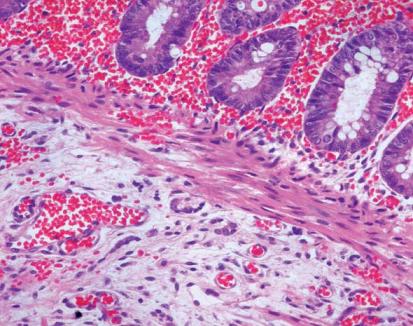

It is also vitally important to determine when a biopsy is insufficient or inadequate for diagnosis. Anatomically, the lower level of sampling is should be one or ideally 2 cms above the pectinate line. Biopsies which are very low or close to the anal sphincter may not have ganglion cells even when the patient does not have aganglionosis. When ganglion cells are not observed in a biopsy and there are islands of squamous epithelium or sphincter muscle fibers, it is the unequivocal signature that the sample was obtained from below the pectinate line. This should always be reported as a sample which is inadequate for diagnosis. If in doubt about the sampling site, I recommend making a note to remind the clinician and avoid misinterpretations. From the histological point of view a rectal biopsy is considered appropriate when the amounts of mucosa and muscularis mucosa together are equivalent in thickness to the amount of submucosa (Figure 6) (10). If the amount of submucosa in the sample is good, but it contains a lymphoid follicle, this must also be considered unsuitable for making a HD diagnosis (Figure 7). For any type of sample received, the pathologist should look judiciously at all cuts. Sometimes neurons can be identified in the periphery of the follicle, or immersed in the muscularis mucosa, in which cases aganglionosis can certainly be ruled out even when biopsies seemed inappropriate for the study (Figure 8).

Figure 6. Adequate biopsy for study of innervation: the submucosal thickness is equivalent to the sum of the mucosa and muscularis mucosa (H&E 40X).

Figure 7. Material unsuitable for study of innervation: the submucosa is largely occupied by a very small lymphoid follicle tissue being evaluated (H&E 40X).